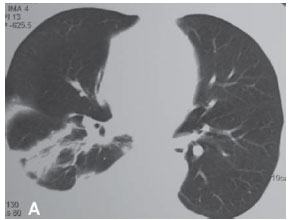

RELATO DO CASOUma mulher de 63 anos, do lar, não tabagista, previamente hígida, apresentou-se com queixa de aumento de volume em pescoço, face anterior do tórax, abdome e membros inferiores. Havia associação com dispnéia discreta aos esforços. O quadro teve início após atividade física leve em academia de ginástica, havia cinco dias. Negava doença pulmonar prévia e referia uso de fluoxetina a 20 mg/dia, bromazepam a 3 mg/dia e reposição hormonal feminina regular. Ao exame clínico observou-se um discreto aumento de volume em fossa supraclavicular esquerda e face lateral direita do pescoço. Observou-se ainda diminuição do murmúrio vesicular de forma difusa e de frêmito toracovocal em bases (direito maior que esquerdo), além de edema de parede abdominal anterior e de membros inferiores (grau I/IV). Foram solicitados hemograma, coagulograma, glicemia, creatinina, uréia, velocidade de hemossedimentação, colesterol total, HDL, triglicerídeos, T3, T4, TSH e parcial de urina, os quais se apresentaram todos normais, descartando a presença de dislipidemia, coagulopatia, infecção, nefropatia e hipotireoidismo. A avaliação radiológica do tórax revelou um pequeno derrame pleural bilateral (Figura 1), confirmado pela tomografia axial computadorizada de tórax (Figura 2A). Esta foi complementada com cortes ao nível do pescoço, que evidenciaram edema na região supraclavicular esquerda com imagem hipodensa (20 x 10 mm) adjacente ao feixe vasculonervoso do pescoço (Figura 2B). A ultra-sonografia da região cervical mostrou a formação de uma coleção cística, posteriormente aos vasos cervicais, sugestiva da ruptura do tronco jugular esquerdo. Demonstrou ainda um pequeno aumento da espessura do músculo esternocleidomastóideo esquerdo, sugestivo de processo inflamatório secundário a distensão muscular (Figura 3). A paciente foi submetida a toracocentese diagnóstica à direita com obtenção de líquido leitoso compatível com QT. A análise laboratorial demonstrou tratar-se de um exsudato com predomínio de polimorfonucleares e com dosagem de triglicerídeos de 2.035 mg/dl, colesterol de 131 mg/dl e proteínas de 9,7 g/dl, confirmando o quadro laboratorial de QT. Foram realizadas citologia oncótica, bacterioscopia de Ziehl, micológico direto e culturas, que resultaram negativos, descartando processos malignos e doenças infecciosas.

O diagnóstico do QT é laboratorial, pois a clínica e os exames de imagens não o confirmam. A tomografia axial computadorizada de tórax é útil para descartar a presença de linfoma ou metástase, mas não auxilia no diagnóstico de QT. O derrame pode ser tanto do lado direito como do esquerdo, dependendo da altura da lesão do ducto torácico. Lesões abaixo de T5 freqüentemente causam derrame no lado direito e, acima de T5, do lado esquerdo. Também foram descritos casos de derrame bilateral.(10) Assim, o diagnóstico é realizado após toracocentese, pela presença de um líquido branco, com pouco cheiro e aparência leitosa.